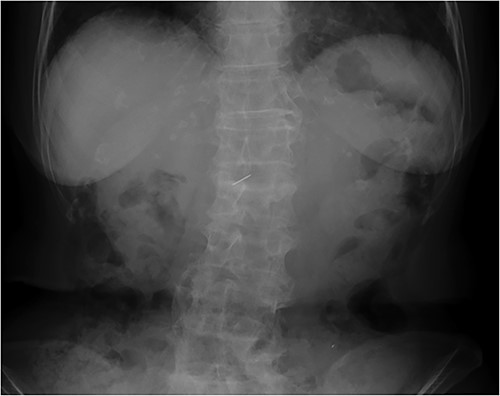

An 81-year-old woman presented to our hospital with an abnormal shadow on her abdominal X-ray performed during a gastrointestinal checkup. She had no subjective symptoms. She had no comorbidities other than hypertension and no history of laparotomy. Her vital signs were normal. No foreign body was palpable on the abdominal wall, chest wall, or back. No mental abnormality or cognitive impairment was noted. A plain abdominal radiograph showed a needle-like shadow at the second lumbar vertebra level (Fig. 1). Abdominal computed tomography (CT) displayed a needle-like shadow obliquely directed from the inferior surface of the liver to the lateral segment. No intrahepatic or intraperitoneal abscess was observed (Fig. 2). Upper gastrointestinal endoscopy revealed no stomach or duodenal ulcer scarring. Detailed history revealed no history of trauma or acupuncture treatment and no memory of accidental ingestion of needles. No subjective symptoms such as sore throat or epigastric pain were reported. Based on these findings, a sewing needle was accidentally swallowed without awareness, perforating at the pylorus of the stomach or duodenal bulb and straying into the liver. The patient had no symptoms at the time of the visit, and we told her that she could be followed up. However, the patient strongly desired needle removal; therefore, we decided to perform a laparoscopic resection. Laparoscopic observation revealed fibrous adhesion between the lesser curvature of the gastric pylorus and the inferior surface of the outer hepatic segment. When the adhesion was detached, the foreign body tip was observed on the subhepatic surface. It was grasped with forceps, extracted, and removed from the abdominal cavity (Fig. 3). A sewing needle of ~3-cm length was removed (Fig. 4). The patient had a good postoperative course and was discharged from the hospital on postoperative Day 4 without any complications.

Abdominal CT scan displaying needle-like shadows obliquely lying in the left lateral segment of the liver.